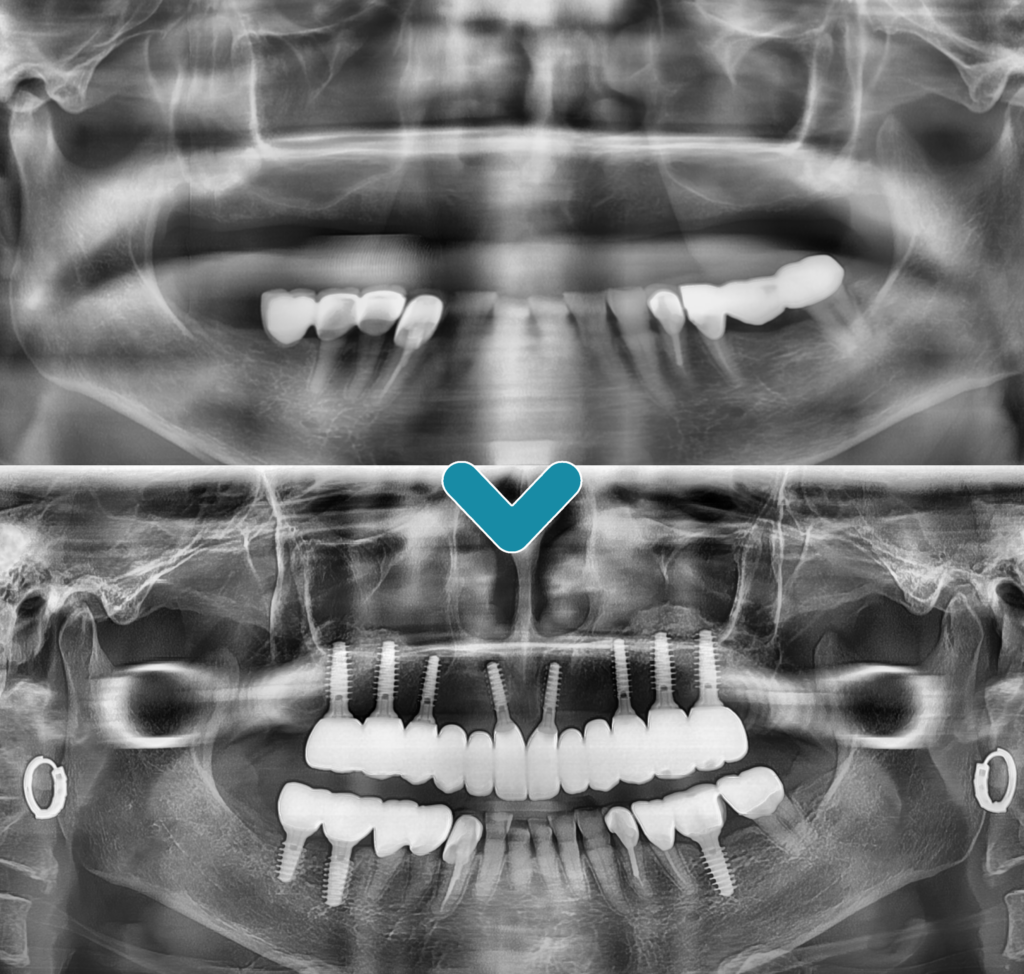

오늘은 상실하신 위쪽 치아 전체를 임플란트로 수복하신 환자분을 소개해 드리려고 하는데요. 오랜 기간 틀니를 사용하시다가 너무 불편하셔서 치료 상담을 위해 내원해 주셨습니다. 임플란트가 처음이셔서 걱정이 많으셨지만 충분한 상담 끝에 최소침습 임플란트를 통해 전체 식립을 진행하시기로 계획을 수립하였습니다.

최소침습 임플란트란 매직코어라고 불리며 잇몸을 절개하지 않는 방식을 사용하여 필요한 만큼만의 구멍을 통해 단기간에 식립할 수 있는 방법으로 연조직과 치조골의 손상을 줄이고, 손상에 따른 환자분의 불편함도 줄여주는 방법을 말합니다.

아래쪽에 예후가 불량한 치아들까지 발치 후 최종 보철물까지 수복을 마친 모습입니다. 이는 치조골 폭이 좁거나 상태가 좋지 않더라도 식립 가능하여, 치조골 크기와 형태에 맞는 임플란트 선택이 가능합니다. 더불어 골이식이나 골 형성 등의 부가적인 수술도 줄여주고 감염이나 부러지는 등의 위험성이 감소하고 강한 보철 구조를 하고 있어 파절이나 나사가 풀리는 것과 같은 부작용이 발생할 우려가 적습니다.

또한, 응력 분산이 뛰어나 내구성이 우수하며, 미세 틈이 없어 음식물 끼임으로 인한 냄새, 염증 등이 감소하므로 건강한 잇몸 생성을 유지할 수 있다는 장점이 있습니다.